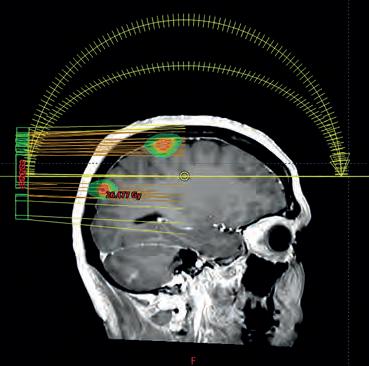

Twintig jaar geleden kon het enkel bij bepaalde hersentumoren, vandaag bij quasi alle organen. Stereotactische radiotherapie evolueerde de afgelopen twee decennia enorm. “Dankzij de hoge dosis stralen kunnen we kleine tumoren sterk verminderen of zelfs volledig genezen. Dat betekent een grote vooruitgang in de overlevingskansen van patiënten.”

Wat is stereotactische radiotherapie en -chirurgie?

Een bestralingsbehandeling waarbij in één of enkele sessies een hele hoge dosis zéér precies wordt toegediend op een klein volume, met als doel de tumor volledig te laten verdwijnen zonder majeure toxiciteit aan het omliggende gezonde weefsel. Stereotaxie is geschikt voor kleinere tumoren of letsels.

2004 – Hersentumoren

“Het LOC was een van de eerste centra in Vlaanderen met stereotaxie voor hersentumoren. De behandeling geeft heel goede resultaten, maar was in het begin erg invasief. De neurochirurgen bevestigden een extern stereotactisch frame met vier schroeven in de schedel van de patiënt. Dat gebeurde onder lokale verdoving. Daarna namen we de voorbereidende CT-scan om de exacte locatie en dosis te berekenen. Pas op het einde van de dag volgde de bestraling. Het frame werd vastgeschroefd aan de tafel om het hoofd perfect te immobiliseren. Erg belastend voor de patiënt en geen optie meer bij herval. Gelukkig gebruiken we vandaag maskers en werken de bestralingstoestellen veel vlotter. Daardoor kunnen we de behandeling gemakkelijker herhalen, ook bij herval of nieuwe letsels. Dat verhoogt de overlevingskansen van de patiënt aanzienlijk.”